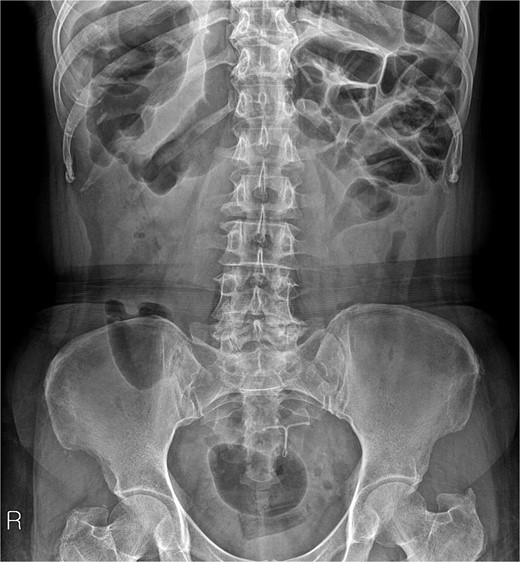

A 54-year-old woman, gravida 4, para 2, presented at the outpatient department with abnormal colonoscopy findings. She had a history of hypertension and underwent an IUD insertion for contraception one year after delivery in 2000. However, in 2007, when she visited the clinic for its removal, the IUD was not found on pelvic examination and ultrasound. The patient assumed that the IUD had been expelled spontaneously. Six months before her 2022 hospital visit, she experienced intermittent rectal bleeding and lower left abdominal pain, leading her to seek medical attention. Her medical history and physical examination, including a digital rectal examination, showed no notable abnormalities except for mild left lower quadrant tenderness. Routine laboratory investigations yielded unremarkable results. During colonoscopy, a foreign body was observed penetrating the sigmoid wall, surrounded by granulation tissue (Fig. 1). Subsequently, an abdominal simple X-ray and computed tomography scan were performed, revealing that the foreign body was an IUD, located next to the left side of uterus and entering the sigmoid colon (Figs 2 and 3).

Foreign body penetrating the sigmoid wall with surrounding granulation tissue observed during colonoscopy.